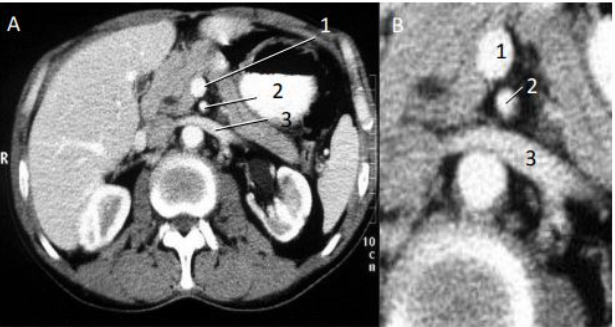

1. VEIA MESENTÉRICA

2.ARTÉRIA MESENTÉRICA

3. VEIA RENAL.